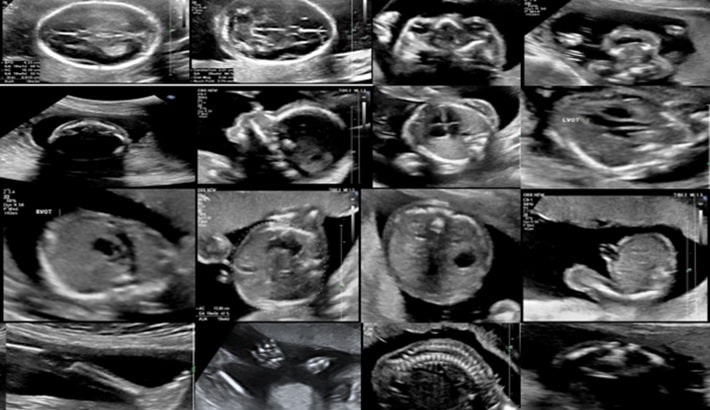

سونوگرافی آنومالی یکی از اصلیترین مراحل بررسی سلامت جنین در دوران بارداری است. این سونوگرافی معمولاً بین هفتههای ۱۸ تا ۲۲ بارداری انجام میشود و هدف آن بررسی جزئیترین قسمتهای بدن جنین است. پزشک با کمک تصاویر دقیق، رشد اندامها و وجود احتمالی ناهنجاریهای مادرزادی را کنترل میکند.

سونوگرافی آنومالی چه چیزهایی را بررسی میکند؟

این نوع سونوگرافی تقریباً همه اندامهای اصلی جنین را بهطور کامل ارزیابی میکند. پزشک بهدنبال اطمینان از رشد طبیعی اندامها و نبود مشکلات ساختاری است.

بررسی مغز و ستون فقرات

با کمک سونوگرافی آنومالی میتوان ساختار مغز و ستون فقرات را بررسی کرد. ناهنجاریهای جدی یا مشکلات مغزی در این مرحله قابل شناسایی هستند.

بررسی قلب و عروق

قلب جنین یکی از اندامهای حیاتی است که باید بهطور دقیق بررسی شود. پزشک با دقت شکل و عملکرد قلب را بررسی میکند تا مشکلات احتمالی قلبی-عروقی تشخیص داده شود.

بررسی اندامهای شکمی و لگنی

اندامهایی مانند معده، کلیهها، مثانه و کبد نیز با دقت بررسی میشوند. وجود یا عدم وجود مایعات در اندامها میتواند اطلاعات مهمی در اختیار پزشک قرار دهد.

بررسی اندامهای حرکتی جنین

دستها، پاها و انگشتان جنین در سونوگرافی آنومالی بهوضوح دیده میشوند. این بخش برای والدین بسیار هیجانانگیز است، زیرا اولین بار است که حرکات کوچک جنین را میبینند.